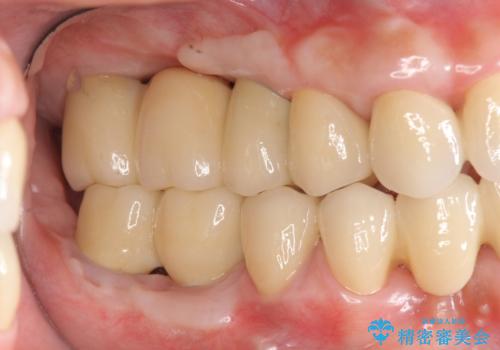

歯周病 全顎治療

- 前歯の見た目、入れ歯による噛めないことの改善を求めて来院されました。

検査により全顎的な歯周病治療、欠損のインプラント補綴、根管治療が必要な状態であることをお伝えし、治療を計画します。

失ってしまった機能を回復し、今後歯を失わないよう残せる歯に歯周病治療を行い、安定した咬合を確立することで長期的に問題なく噛めるような口腔内環境を達成できるようになると考えます。